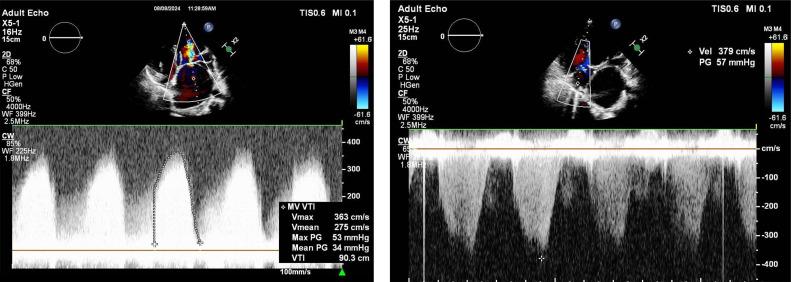

Cor triatriatum is an uncommon cardiac defect that occurs in 0.1-0.4% of congenital heart disease patients. It is characterized by a fibromuscular membrane separating the left (sinister) or the right (Dexter) atriums in tow chambers. The disease is usually discovered accidently in late childhood, usually as a result of a moderate form of this condition type. We discuss the case of a 14-year-old girl who had been experiencing exertional dyspnea and palpitations for about a year. She was referred to our hospital for assessment after an initial echocardiogram at another hospital revealed a mass around the left atrium. Repeated echocardiography at our institution revealed dilated coronary sinus, confusing the diagnosis. The left atrium was dilated and divided into 2 chambers by a thin membrane with an elevated pressure gradient between the 2 chambers. Cardiac CT and MRI confirmed the diagnosis of cor triatriatum sinister (CTS) with concomitant persisting left superior vena cava. Because of her symptoms, she was started medical treatment and referred for surgical evaluation. Cor triatriatum sinister (CTS) is frequently accompanied with atrial septal abnormalities and enlarged coronary sinus caused by a persistent left superior vena cava, as demonstrated in our case. The management of cor triatriatum sinister (CTS) is determined by the severity of the symptoms. Asymptomatic individuals with no pressure gradient do not require therapy; however, significant membrane obstruction may require surgical removal, which typically leads to positive short- and long-term outcomes.

三房心是一种罕见的心脏缺陷,在先天性心脏病患者中发生率为0.1%-0.4%。其特征是有一个纤维肌性膜将左心房(左位)或右心房(右位)分隔为两个腔室。该病通常在儿童晚期偶然发现,通常是这种病情的中度形式导致的。我们讨论一例14岁女孩的病例,她出现劳力性呼吸困难和心悸约一年。在另一家医院进行初步超声心动图检查发现左心房周围有肿物后,她被转诊至我院进行评估。我院重复进行的超声心动图检查显示冠状窦扩张,这使诊断变得复杂。左心房扩张,被一层薄隔膜分为两个腔室,两个腔室之间存在升高的压力梯度。心脏CT和MRI确诊为左位三房心(CTS)并伴有持续左上腔静脉。由于她的症状,她开始接受药物治疗并被转诊进行手术评估。如我们的病例所示,左位三房心(CTS)常伴有房间隔异常和由持续左上腔静脉导致的冠状窦扩大。左位三房心(CTS)的治疗取决于症状的严重程度。无症状且无压力梯度的个体不需要治疗;然而,明显的膜性梗阻可能需要手术切除,这通常会带来良好的短期和长期预后。